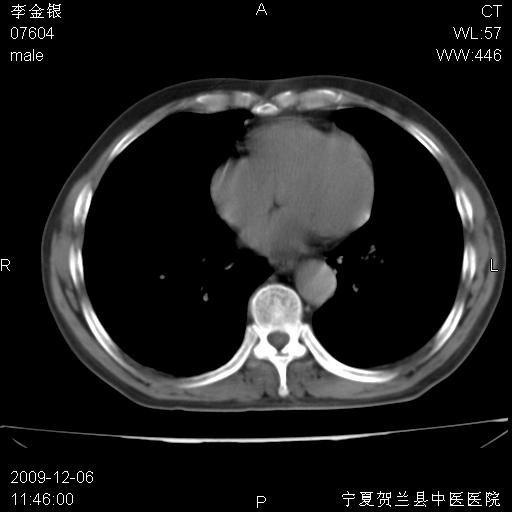

该病人 ,男,62岁,主因咳痰带血两天

考虑右肺中心型肺癌伴阻塞性肺炎及右肺门淋巴结转移,建议纤维支气管镜进一步检查。

支气管壁明显增厚 管腔狭窄,腔静脉后多个淋巴肿大,结合年龄病史考虑右肺上叶中央型肺癌并阻塞性肺炎

符合中央型肺癌的ct表现并肺出血。但有一点腔静脉后有一钙化的淋巴结啊

右肺中心型肺癌伴阻塞性肺炎及右肺门与纵膈淋巴结转移很典型,可纤维支气管镜进一步检查

右侧中央型肺癌伴纵隔内淋巴结转移考虑。

考虑右侧中央型肺癌伴右肺上叶后段阻塞性炎症、肺不张、右肺门和纵隔淋巴结肿大。

右肺上叶中心型肺癌,阻塞性肺炎、右肺门和纵隔淋巴结转移。